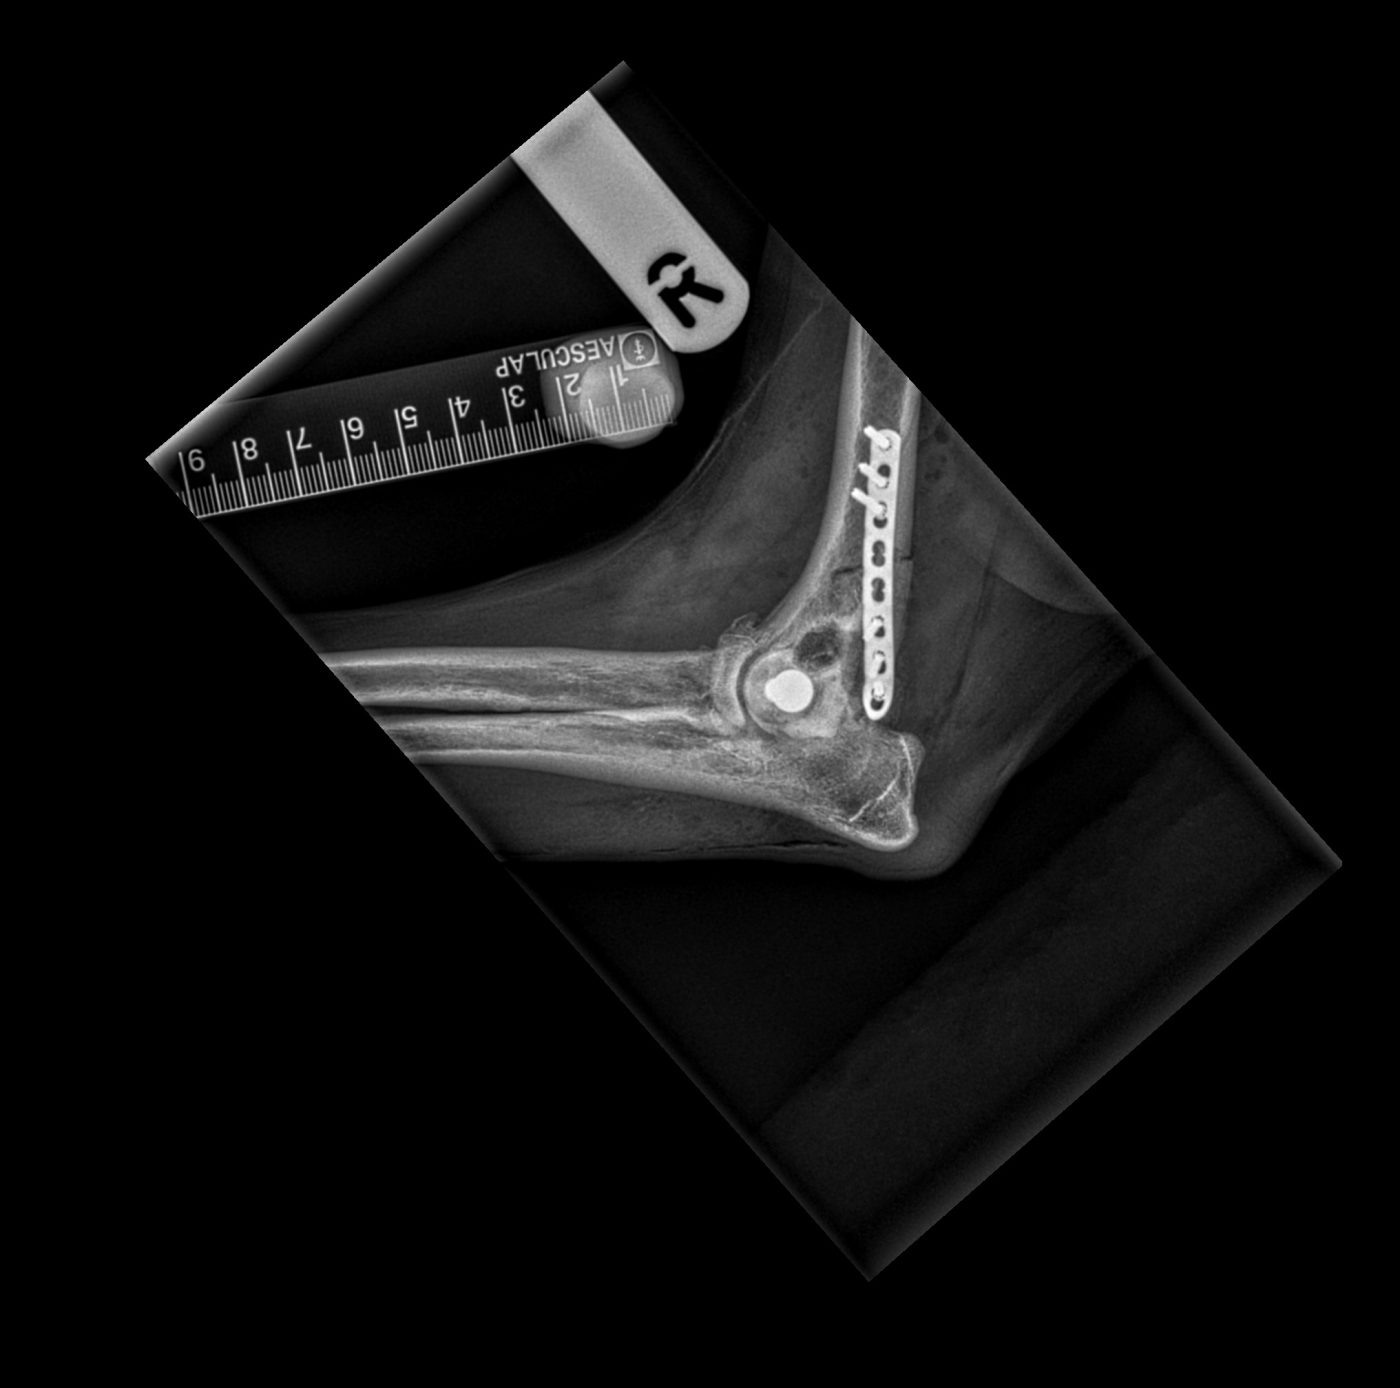

Surgical repair was required, and this was performed by practice principal Dr Martin Hobbs and senior veterinary surgeon Dr Rupert Davenport. A CT scan was carried out prior to the surgery to assist with pre-surgical planning. After incision, the fractured bone was manipulated back into a normal anatomical position, and secured in place using plates and screws. The site was closed using dissolvable sutures, and post-operative x-rays confirmed the surgery had been successful.